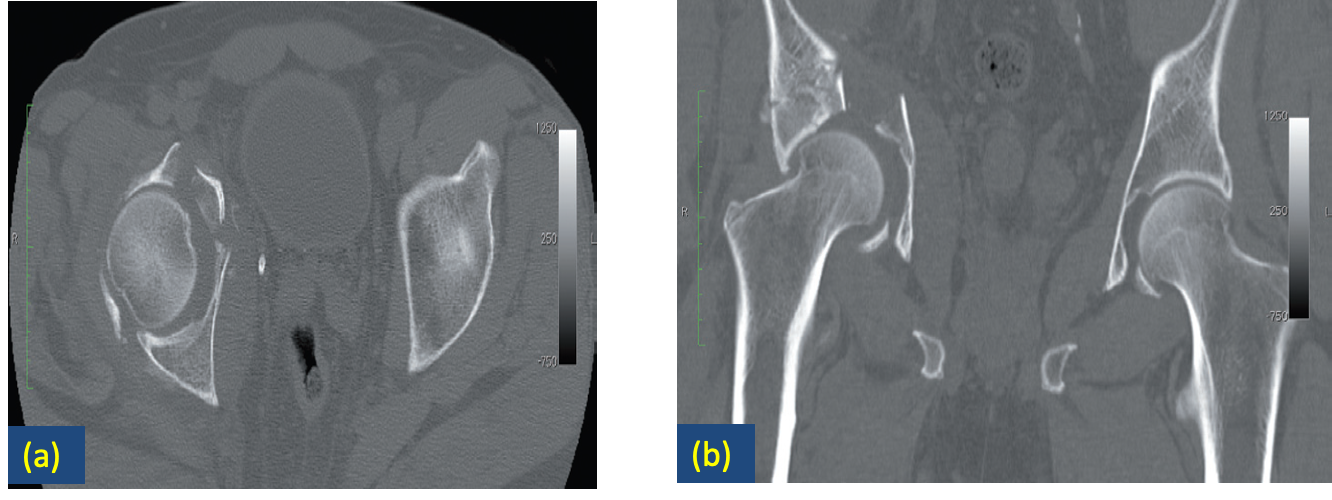

Fracture of the pelvis.

(A) section through the acetabular roof demonstrating an anterior column injury with displaced bony fragments.

(B) A coronal section showing the fracture of the acetabulum extending to the iliac bone superiorly.

The fractures and their displacement were much better demonstrated with CT than with radiographs of the pelvis.